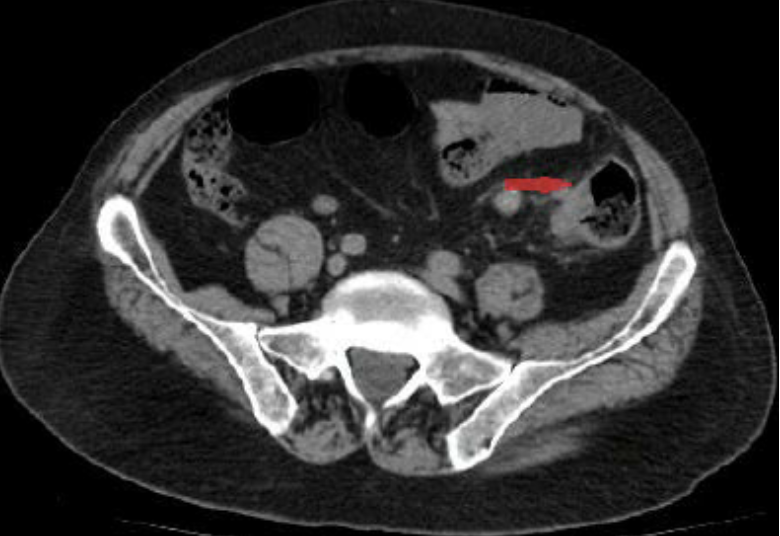

Acute appendicitis

CT Abdomen/Pelvis IV contrast

Diverticulitis

CT Abdomen/Pelvis IV contrast

Intra-abdominal abscess

CT Abdomen/Pelvis IV contrast

Colonic mass

CT Abdomen/Pelvis IV contrast